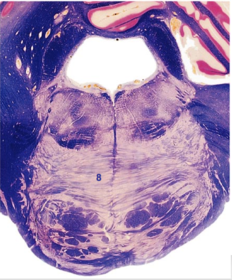

| Nucleus gracilis | |

| Accessory nucleus | |

| Medial longitudinal faciculus | |

| Pyramidal decussation | |

| Medullary pyramids | |

| Anterior spinocerebellar tract | |

| ALS | |

| Posterior spinocerebellar tract | |

| Spinal tract of V | |

| Spinal nucleus of V | |

| Nucleus cuneatus | |

| Fasciculus cuneatus | |

| Fasciculus gracilis | |

| Central canal | |

| Internal acruate fibers | |

| Lateral (external/accessory) cuneate nucleus | |